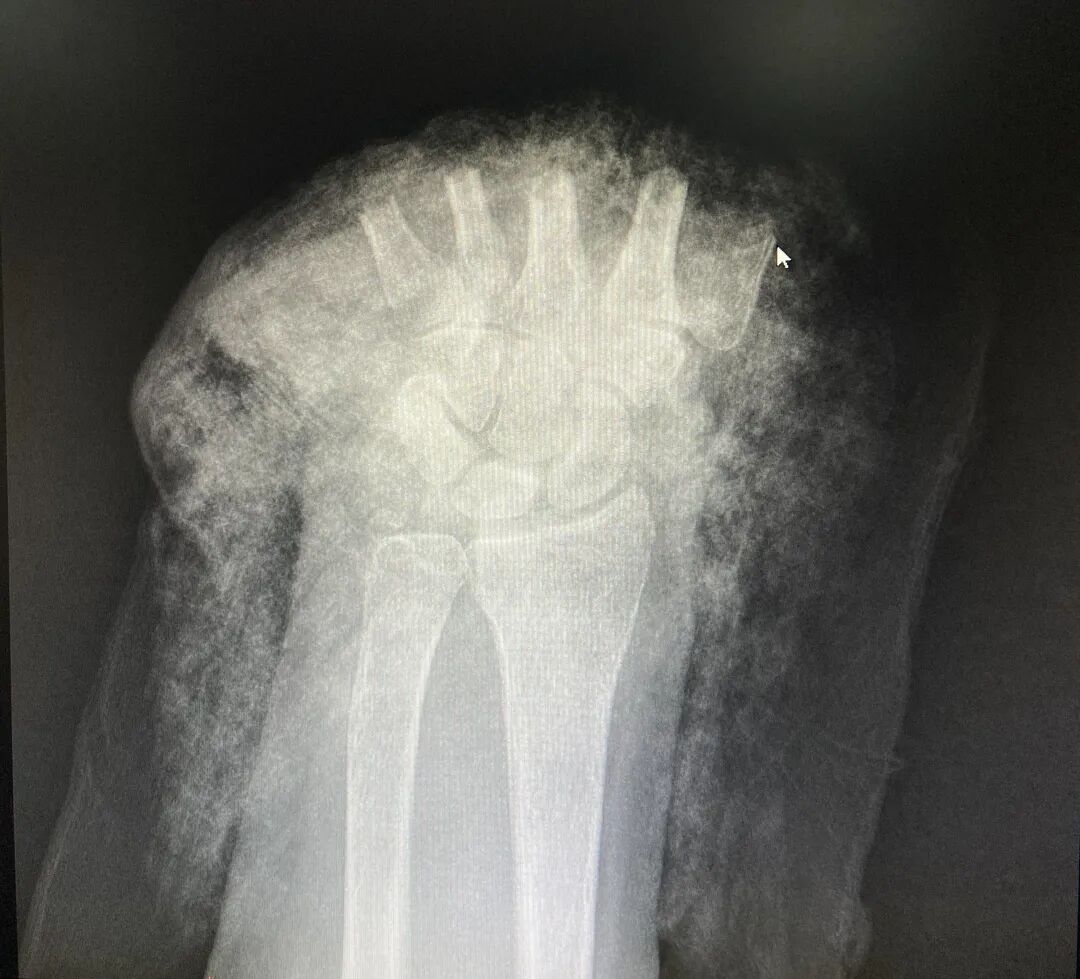

断掌正面CT图 断掌侧面CT图

5小时手术断掌残垣 “截”后余生

“因牵牛而导致断手的病例还是头一次看到。”树兰(杭州)医院手足显微外科黎斌副主任医师接诊后表示:“伤者由于手掌被麻绳勒紧,受到前后牵拉力同时作用而造成手掌骨头、肌腱及神经组织断裂,属于非常严重的旋转撕脱离断伤。”

黎斌副主任介绍介绍,手足显微外科经常会接诊被机器或者刀具砍伤的手部受损,断面比较整齐,但张奶奶这种撕扯伤有很多缺损组织,因拉扯被抽出的肌腱长度达20多厘米,比砍断更严重,大大增加了再植手术的难度,因此当时伤者送到医院时已经面临截肢的危险。